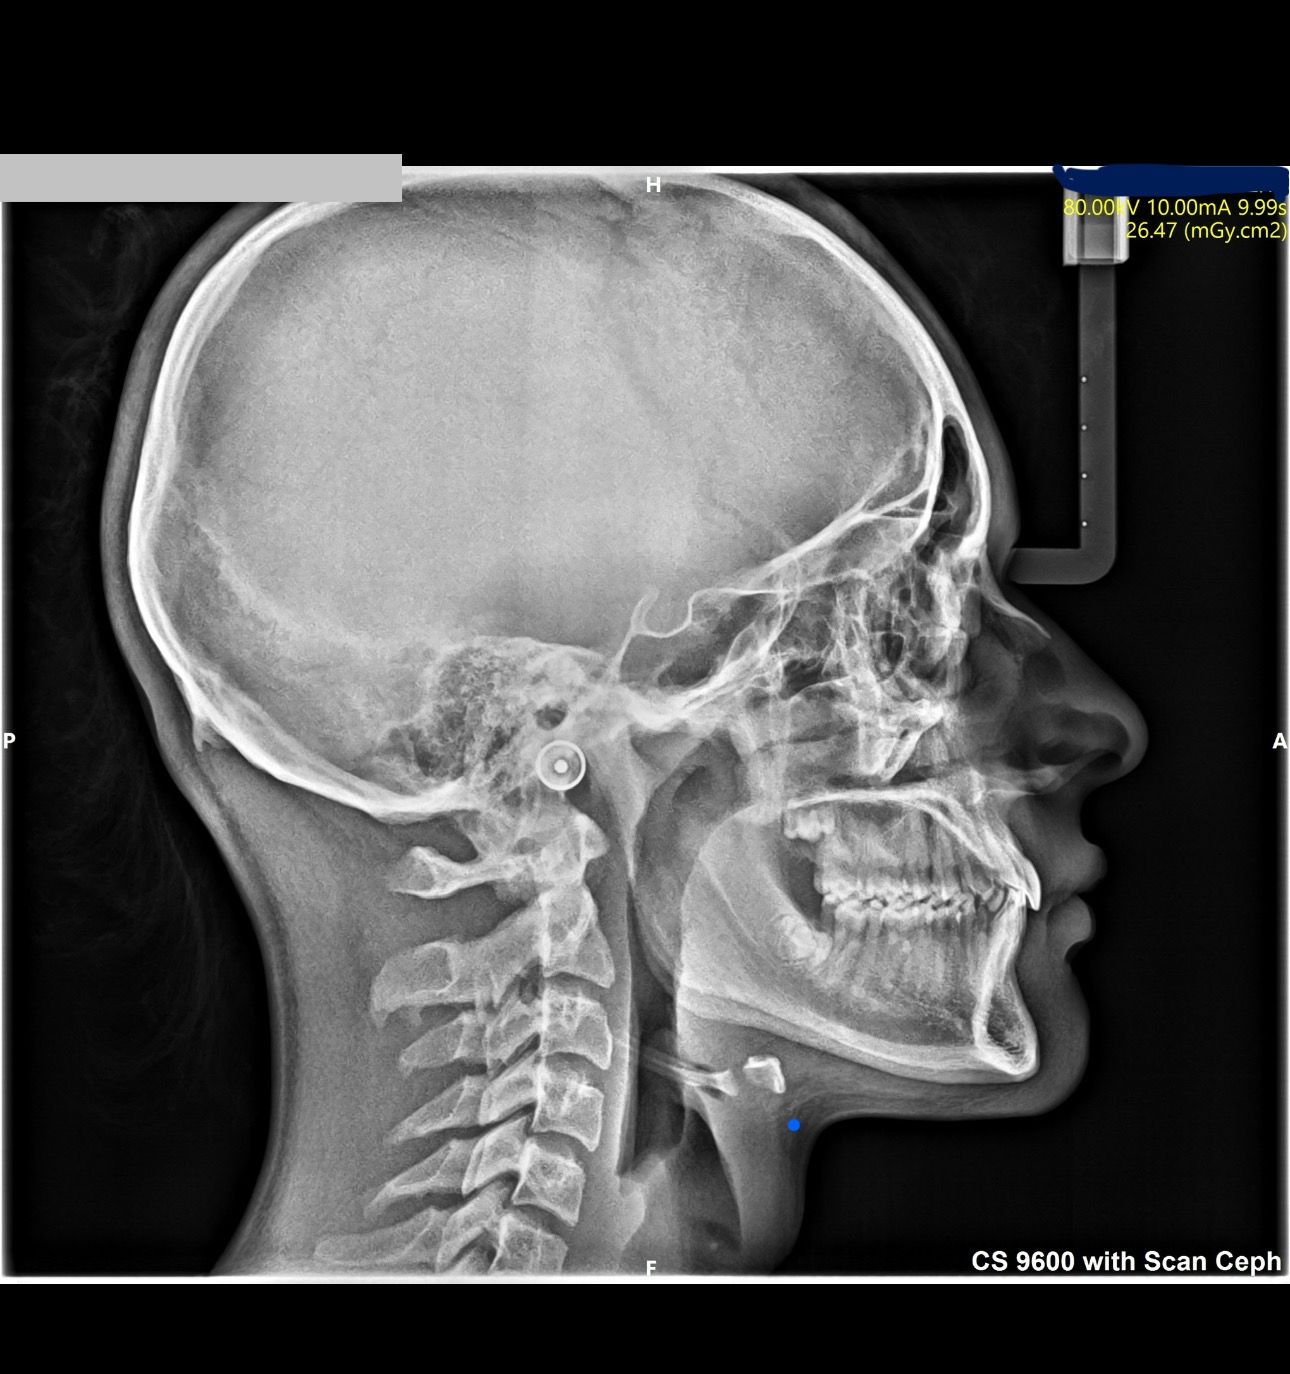

just made a few scans and im considering palete expander of face mask, ideally both?

IMG 7914

i was thinking of:

Rapid Palatal Expander (RPE) + generic face mask

any other tip/recommendation is highly appreciated